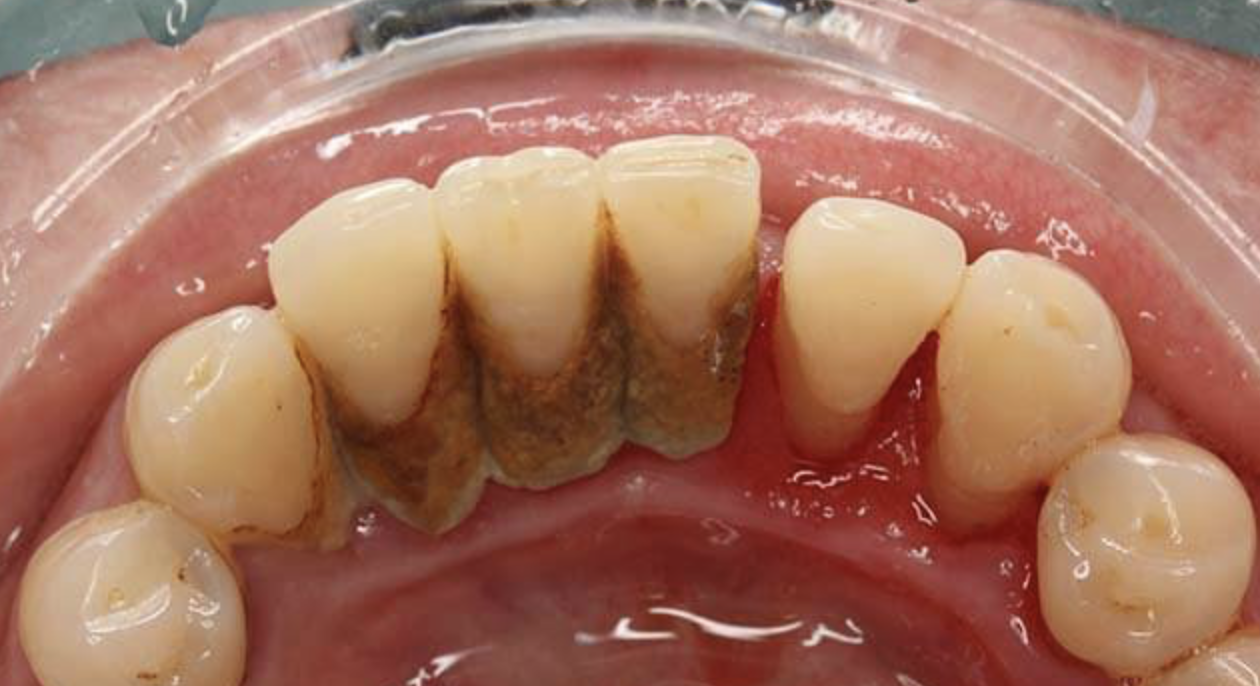

麦芽口腔指出,生活中常见的牙龈出血都是牙性的,没有全身性的不适,表现为刷牙、进食、吸吮时牙龈出现渗血。导致牙龈出血的原因除了硬物撞击导致的牙龈受伤,更多是口腔卫生引起的。

2、口内牙周环境较为复杂:

尤其针对牙周炎患者来说,存在牙周袋,牙菌斑与牙结石多附着于龈下,尤其容易导致牙龈炎症。